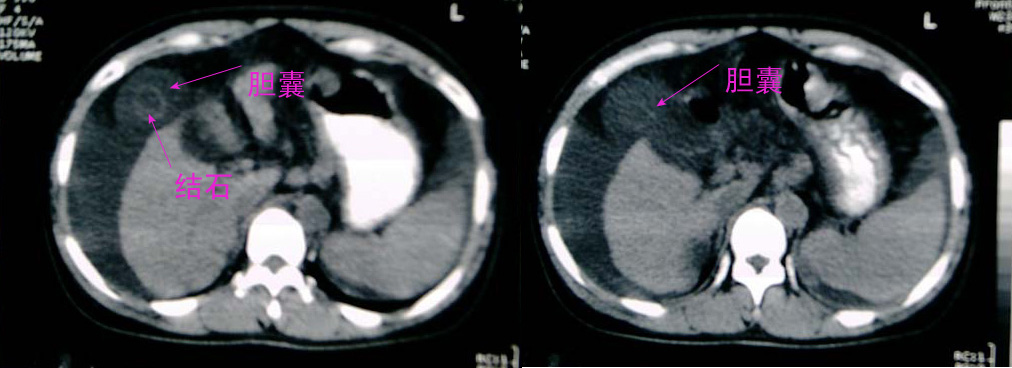

大家好,还有就是她的胆囊在哪?那肝右前间隙液体内环状稍高密度是什么,又为什么壁欠光滑.请大家再帮忙看看.

肝右前间隙液体内环状稍高密度,不会就是胆囊吧?

支持肝硬化、腹水、脾稍大。肝脏与前腹壁的环状影考虑是胆囊及胆囊结石。

肝右前方就是胆囊,胆囊小,壁增厚。

支持肝硬化、腹水、脾大。,另腹水内漂浮的圆形阴影考虑:1 胆囊 2 大量腹水后继发感染形成脓肿。

支持楼上:肝硬化腹水脾大,胆囊炎并结石;

[quote]以下是引用501959462在2006-10-23 19:26:00的发言:[br]大家好,还有就是她的胆囊在哪?那肝右前间隙液体内环状稍高密度是什么,考虑就是胆囊!